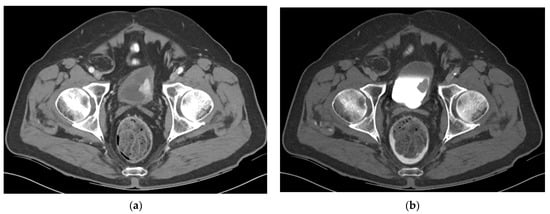

5.1. Computed Tomography (CT)

- Lee, C.H.; Tan, C.H.; Faria, S.C.; Kundra, V. Role of Imaging in the Local Staging of Urothelial Carcinoma of the Bladder. AJR Am. J. Roentgenol. 2017, 208, 1193–1205. [Google Scholar] [CrossRef] [PubMed]

- Vikram, R.; Sandler, C.M.; Ng, C.S. Imaging and staging of transitional cell carcinoma: Part 1, lower urinary tract. AJR Am. J. Roentgenol. 2009, 192, 1481–1487. [Google Scholar] [CrossRef]